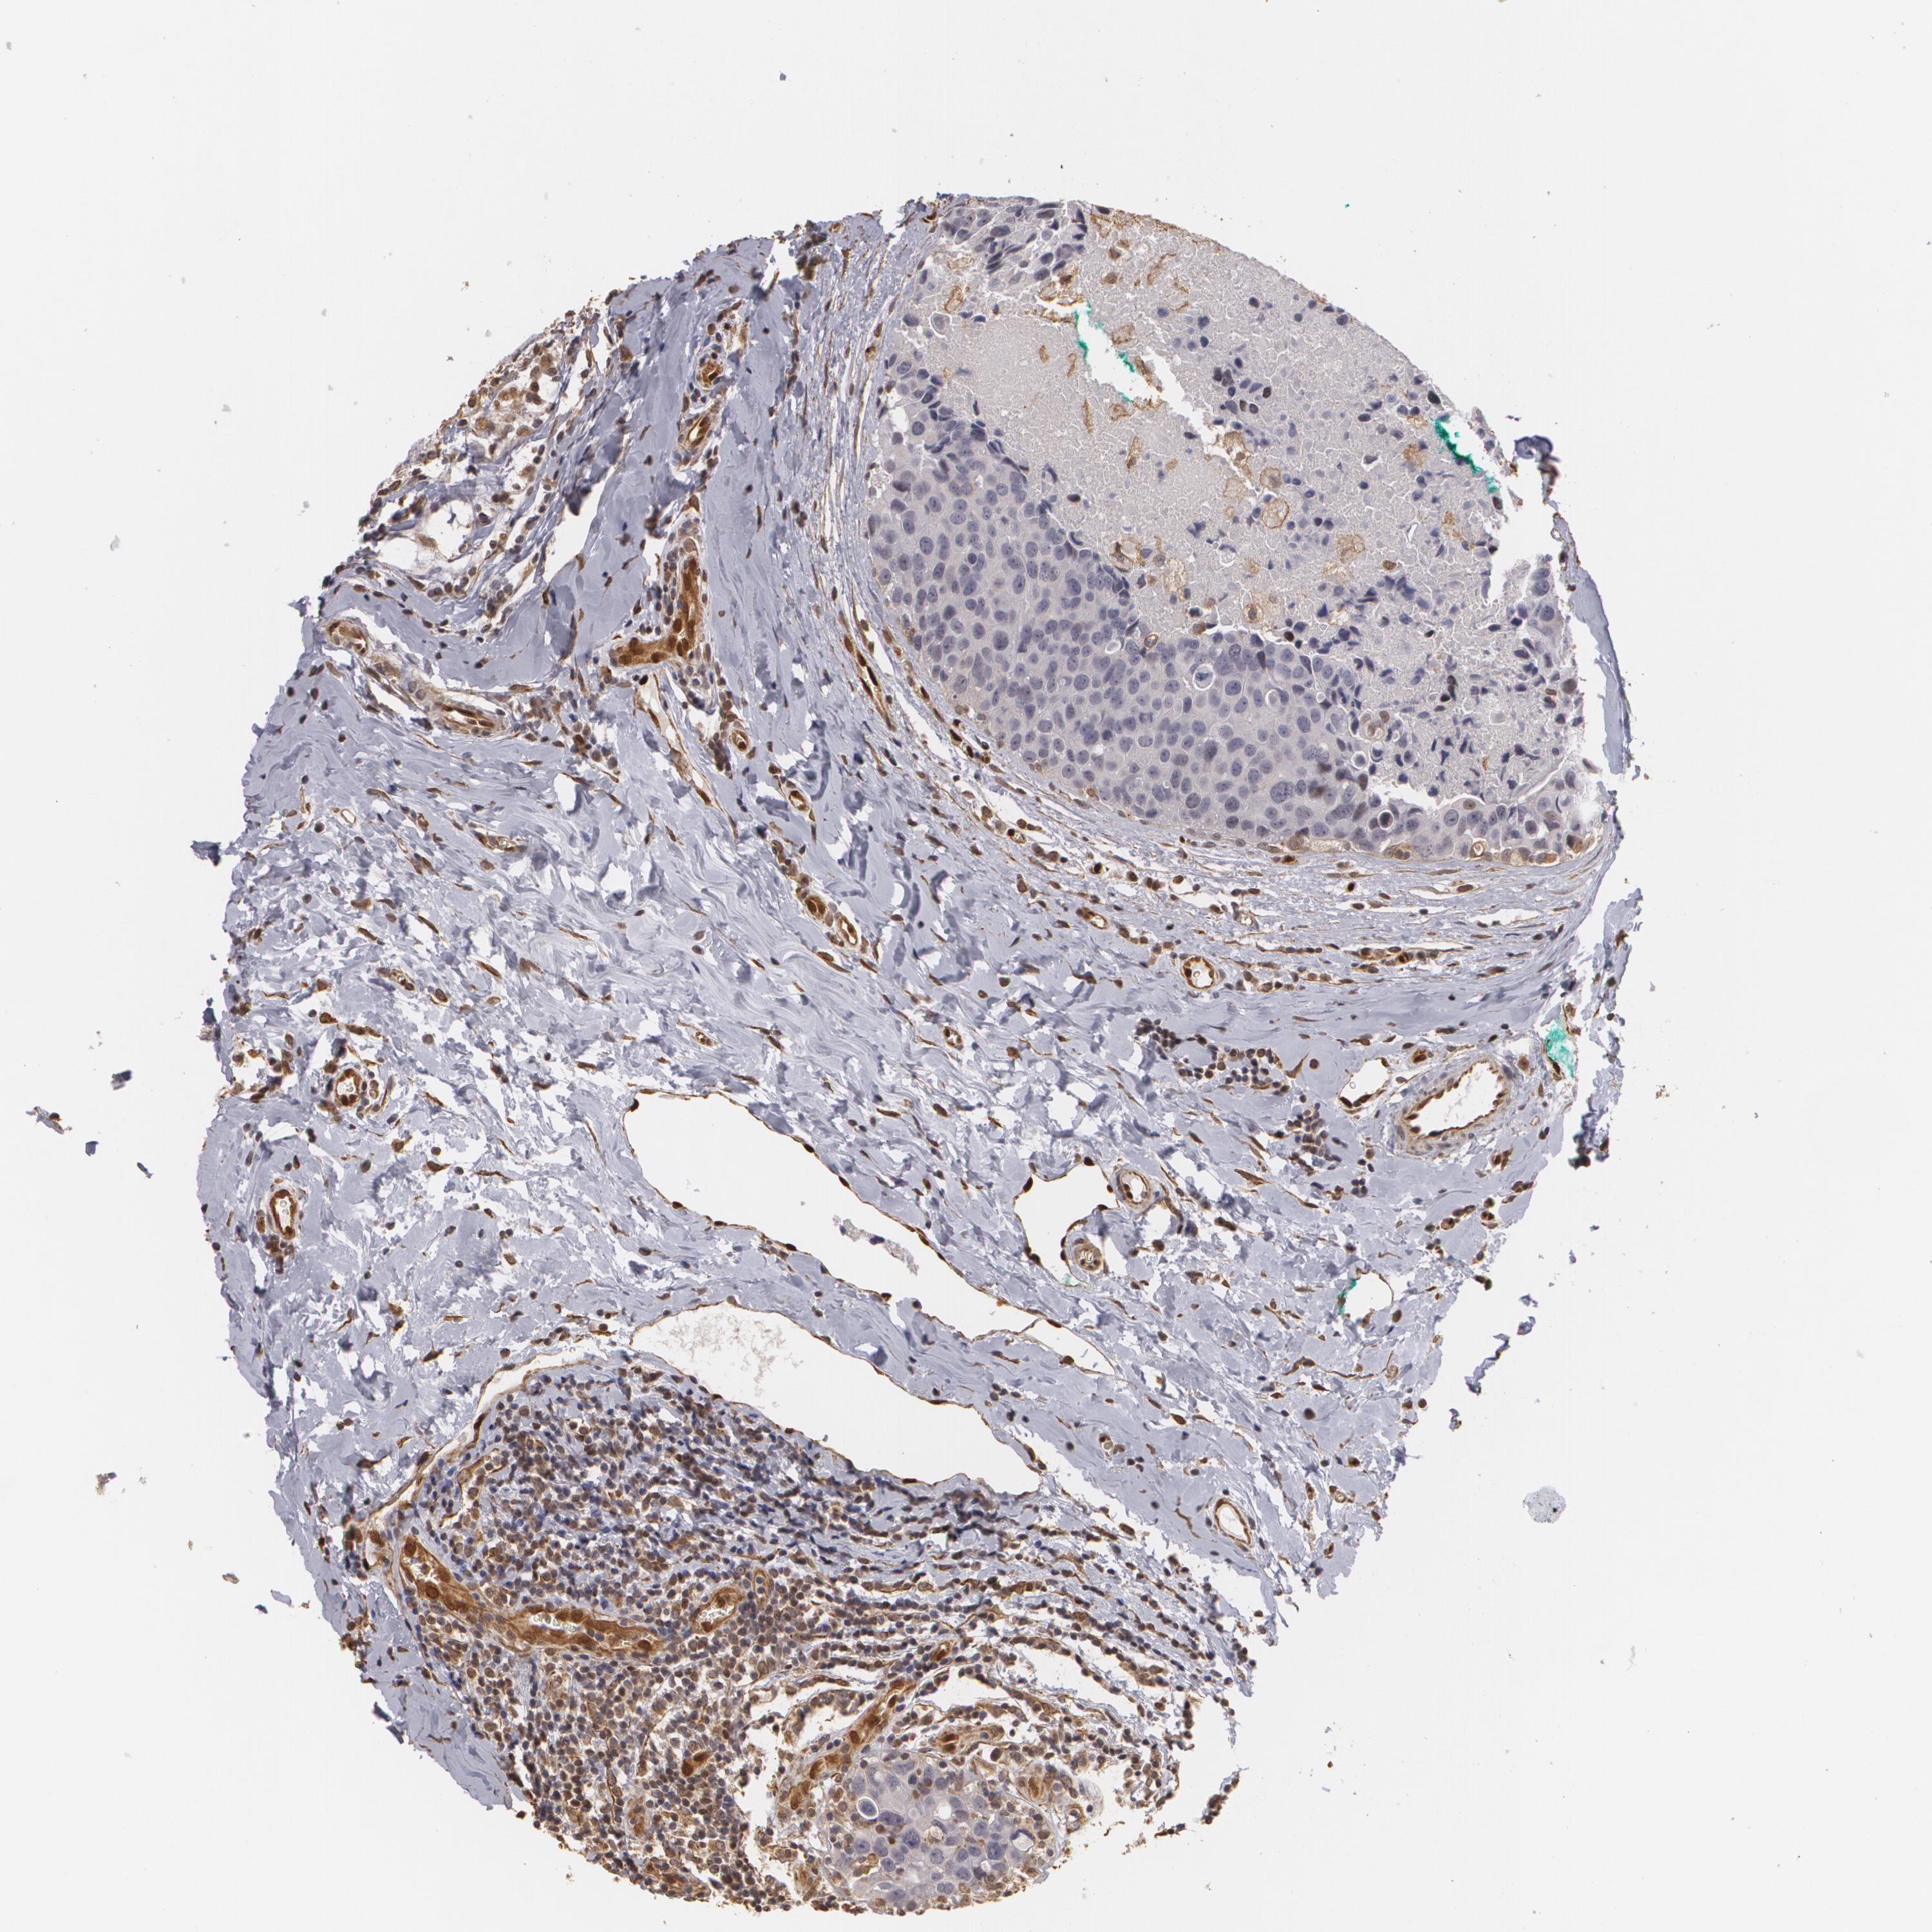

BRCA TCGA BRCA VALIDATION PROTEIN EXPRESSION

ANTIBODIES

AND

VALIDATION